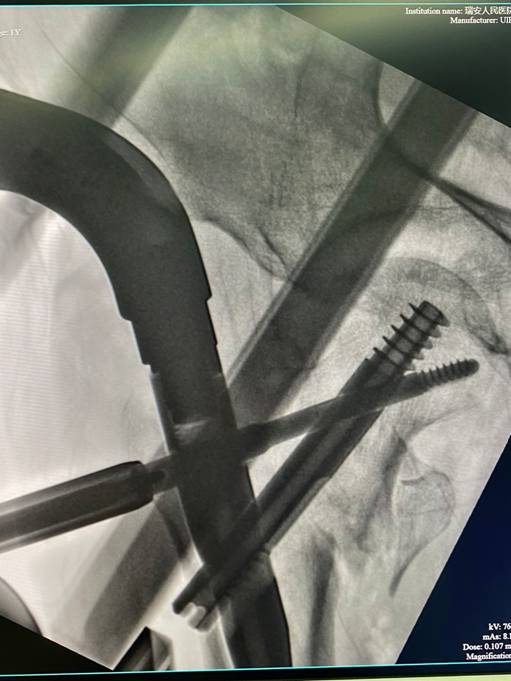

术前准备完善后,张英泽指导创伤骨科团队开展手术,一边指导手术操作,一边向在场医护人员讲解手术操作要点及技巧,讲解PFBN股骨近端仿生髓内钉内固定系统的创新固定理论。患者术中出血约100毫升,仅用30分钟、2个小切口(1-2cm),便圆满地完成了手术。张英泽院士高超的手术技术及详细的技巧讲解让在场医护人员受益匪浅。该患者的手术由创伤骨科主任王伟良及谢秉局主任医师共同协助完成。

股骨近端仿生髓内钉系统(PFBN)是基于张英泽的“三角稳定结构”原创专利和张殿英创立的“杠杆平衡重建”理论上共同研发而成的我国原创的全仿生股骨近端髓内钉内固定系统。其设计理念能够使股骨近端支点位置得到最佳恢复,在术后早期即可提供坚强的固定作用,且在骨折术后愈合及功能康复过程中能有效地提供持续而稳定的固定作用,同时有效降低甚至避免传统髓内钉治疗时面临的“退钉、旋转、切割、不稳定”四大难题,明显缩短了患者下地时间,提高了治疗效果。为老年髋部骨折患者提供了一个全新的微创手术内固定选择。

(图为患者术后当场C臂机拍摄影像)